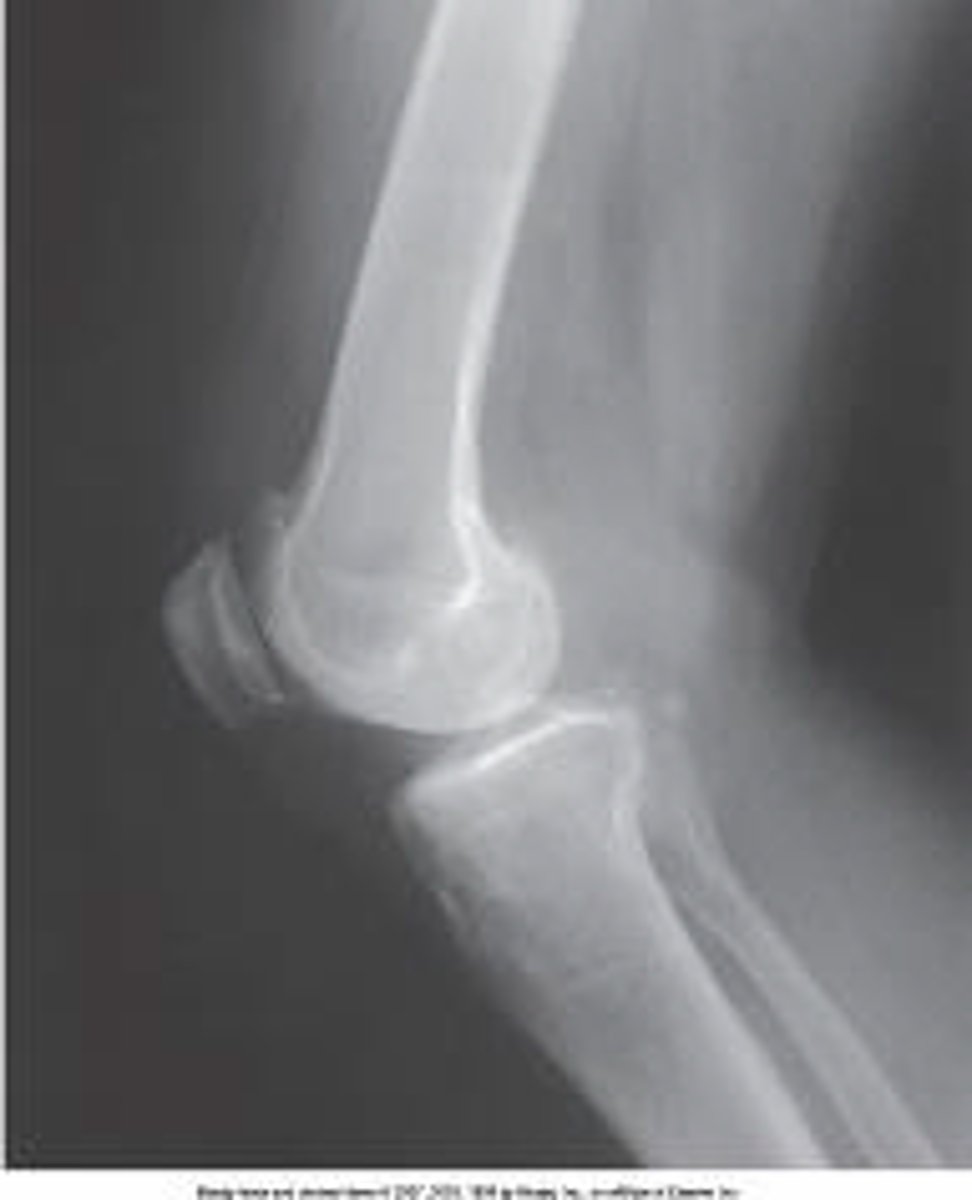

What projection is demonstrated in the image below?

AP oblique knee with medial rotation

AP knee

AP oblique knee with lateral rotation

PA knee

5 to 7 degrees cephalic

What is the central-ray direction needed to produce the image below?

Perpendicular

3 to 5 degrees cephalic

10 degrees cephalic

Proximal tibiofibular joint

What anatomy is labeled with the letter B in the image below?

Lateral femoral condyle

Lateral tibial condyle

Tibial tuberosity

What anatomy is labeled A in the image below?

Patella

Medial femoral condyle